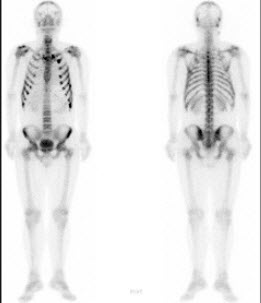

41、多项选择题

男,21岁,临床诊断胃癌,诉全身多处骨关节疼痛,行全身骨显像如图,对此影像下列描述正确的是()

A.胸12椎体放射性“冷区”

B.若同时X线检查为阴性则提示骨转移可能性大

C.“冷区”的出现一定表明骨转移

D.患者胸骨浓聚提示骨转移

E.胸12椎体可能存在肿瘤的骨髓浸润